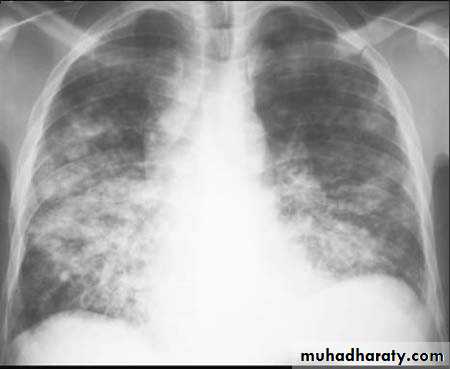

Lobular consolidation ( broncho pneumonia )

Very important to consider that pulmonary edema in normal sized heart have close similar appearance to broncho pneumonia

The important Golden Key differentiation is the cardiac size being enlarged in pulmonary edema .

36.lobuler consolidation (lobular pneumonia )37.discussion

Post primary TB broncho pneumoniacotton wool sign

Post primary TB Bronch pneumonia